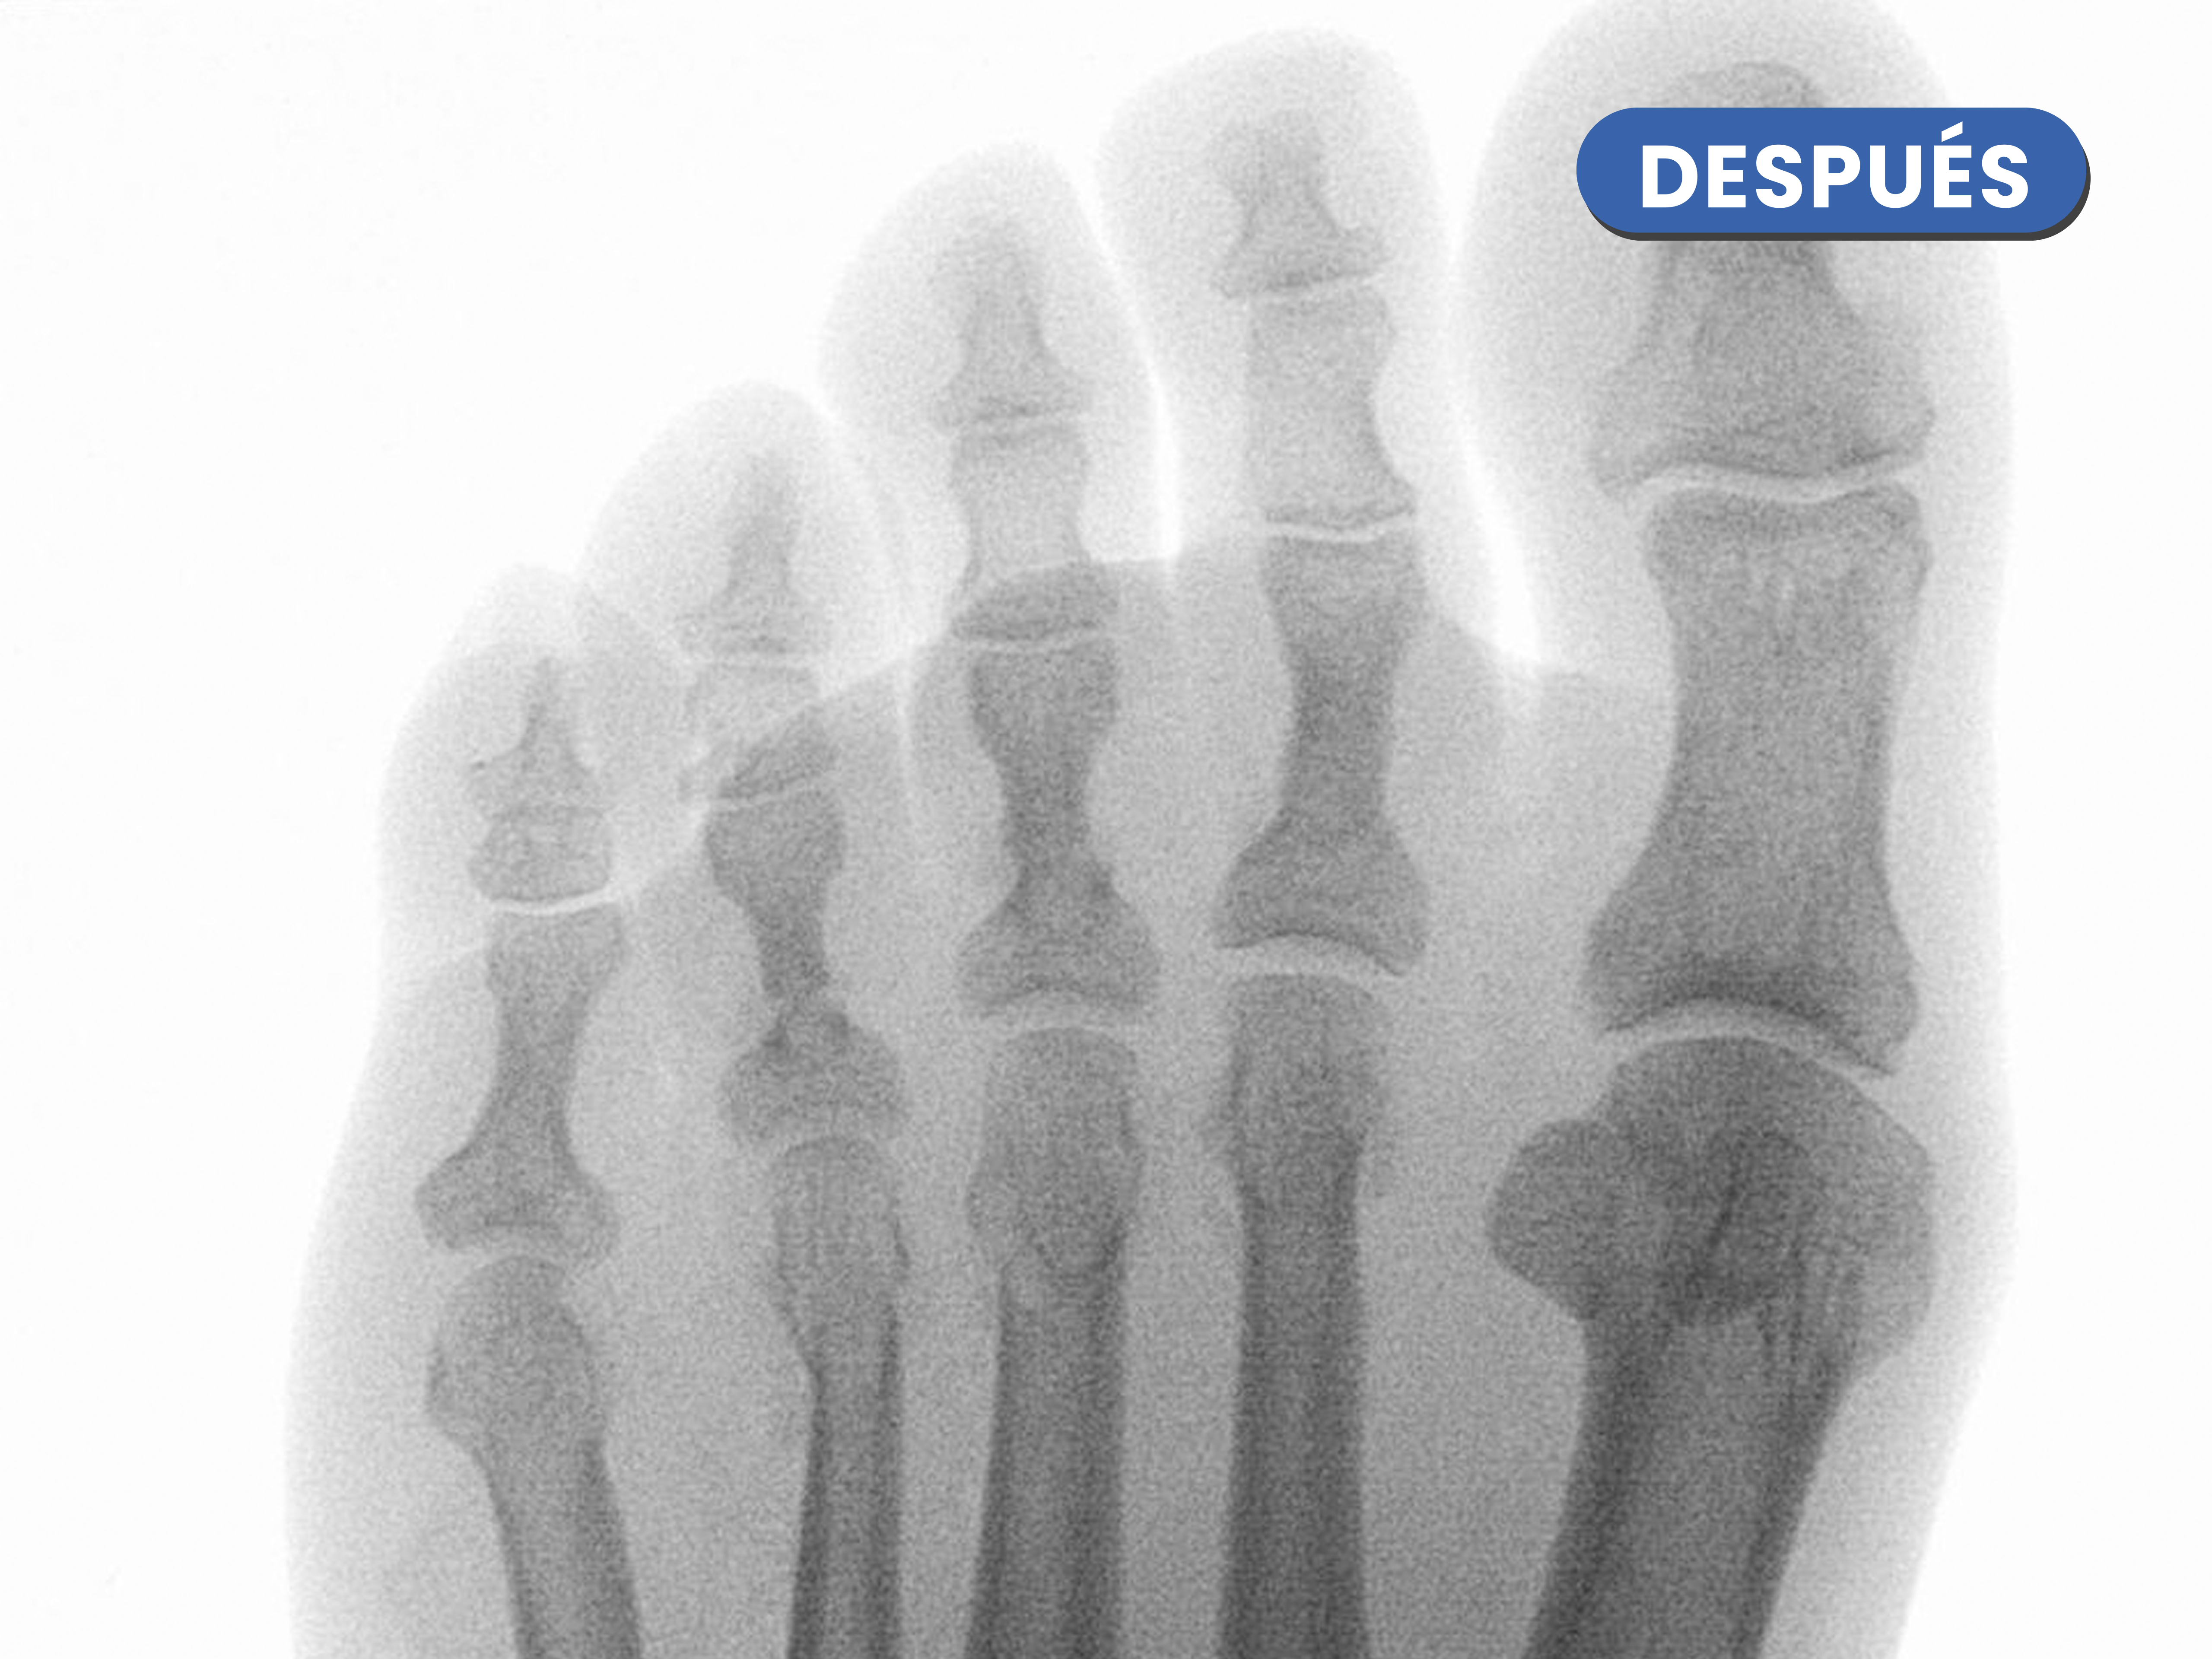

En este caso realizamos una osteotomía acortadora del tercer metatarsiano al ser más largo estaba creando una sobrecarga en la zona, se puede visualizar como disminuye de tamaño en la imagen de después de la cirugía.